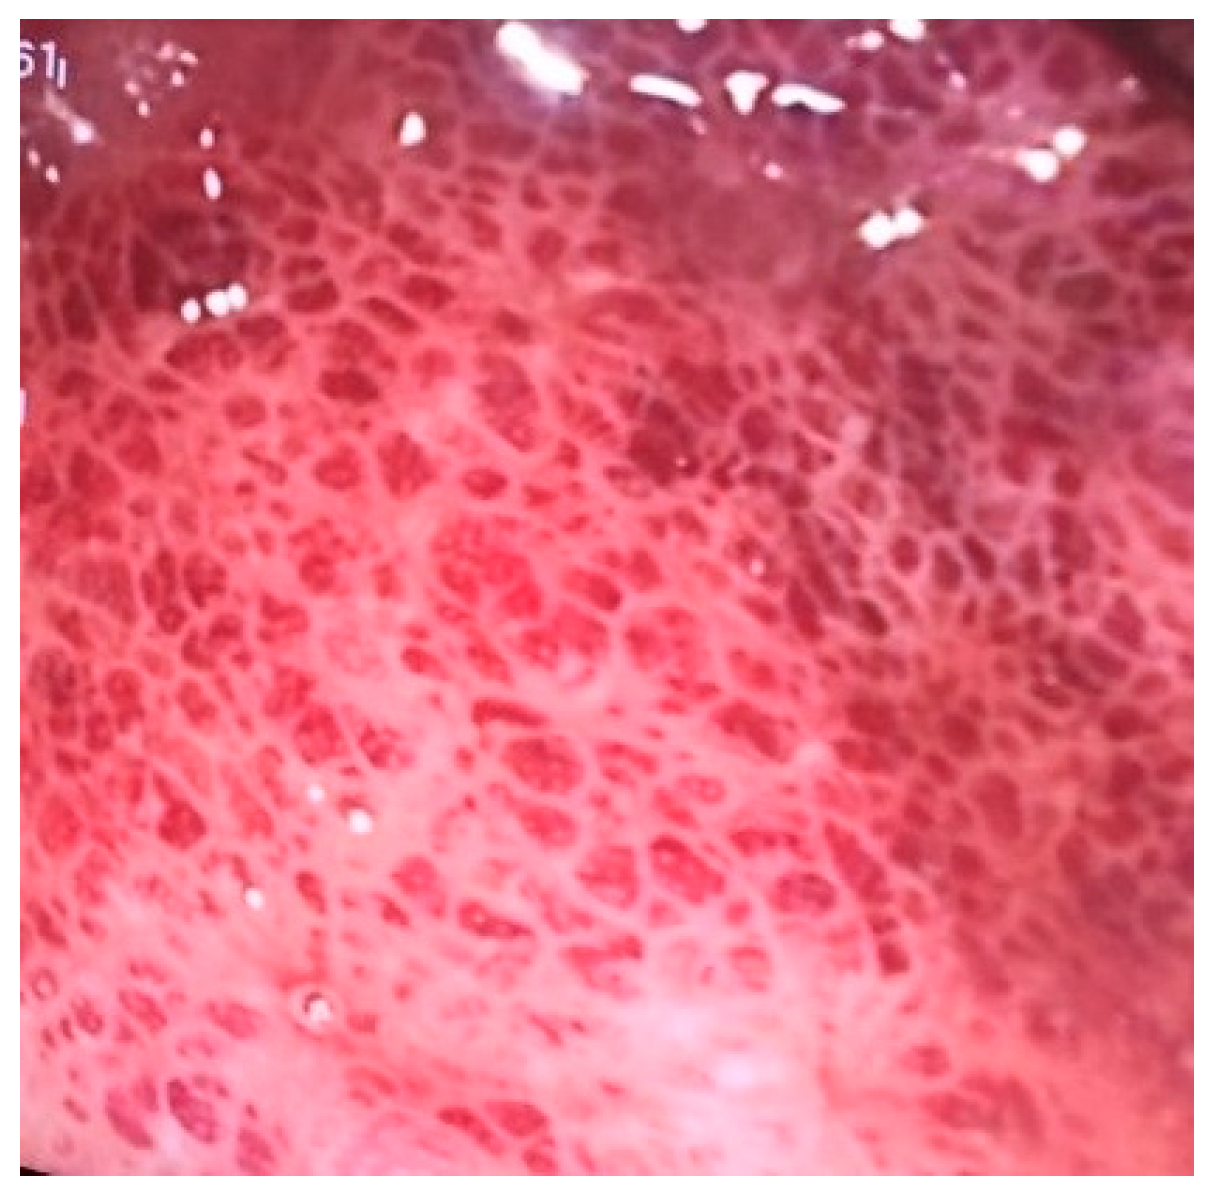

A 38-year-old female patient, previously healthy, presented with a history of hematochezia up to 8 times per day, followed by abdominal cramps, urgency, and chills for two days. She denied having traveled or having ill contacts, and she did not recall taking any food or medication that could be the cause of her symptoms. She did not have any respiratory symptoms and was previously vaccinated for COVID-19. During physical examination, she was afebrile, with a blood pressure of 110/70 mm Hg, pulse of 60 bpm, and oxygen saturation of 98%, and an abdominal examination showed tenderness in the left lower quadrant of the abdomen. Blood samples showed a normal complete blood count, C-reactive protein (CRP) level of 66 mg/L, fibrinogen level of 4.1 g/L, and D-dimer level of 2302 mcg/L FEU. Stool samples for stool culture, Clostridioides difficile, and viral examination were taken, and they came back negative. She received azithromycin 500 mg/day for 3 days and rehydration. On day 3 after the first visit, her CRP levels rose to 89 mg/L, and she reported a mild cough, fever, and loss of smell and taste. A nasopharyngeal swab for SARS-CoV-2 polymerase chain reaction (PCR) test came back positive. On day 6, the patient still had hematochezia accompanied by abdominal cramps, but fever and respiratory symptoms withdrew. CRP level, fibrinogen, and D-dimers were still elevated. Additionally, aspartate aminotransferase (AST) and alanine aminotransferase (ALT) became elevated (78 U/L and 61 U/L, respectively). Gastroenterologist was consulted, and sigmoidoscopy was performed. Sigmoid mucosa showed hyperemia, submucosal bleeding, and erosions (Figure 1); changes were less prominent in rectal mucosa. Biopsies were taken from sigmoid colon and rectum for histology and for PCR SARS-CoV-2 testing (FTD SARS-CoV-2 Assay, Fast Track Diagnostics, Luxembourg). Computed tomography (CT) angiography of mesenteric blood vessels was performed and showed no signs of thrombosis in superior or inferior mesenteric vein or artery, and there was no bowel wall thickening. Histology showed plasma cell and neutrophil infiltration in lamina propria, cryptal abscesses, and cryptal destruction (Figure 2). A PCR test for SARS-CoV-2 virus from colonic biopsy sample was positive. The viral load of the respiratory specimen was higher than that of the rectal specimen, based on the Ct values. The patient was treated with methylprednisolone iv. for two days and peroral prednisone afterwards, with mesalamine orally and rectally, metronidazole orally and enoxaparin. On day 11, the patient was feeling better, with 5–6 normal stools per day with traces of blood; the blood samples showed normal CRP, AST and ALT, fibrinogen 3.7 g/L, and D-dimers 1332 mcg/L FEU. A control sigmoidoscopy was performed two weeks after the first one and showed only mucosal hyperemia (Figure 3). The patient eventually recovered completely with no residual symptoms.

Figure 1. Sigmoidoscopy image of COVID-19 colitis showing submucosal bleeding.